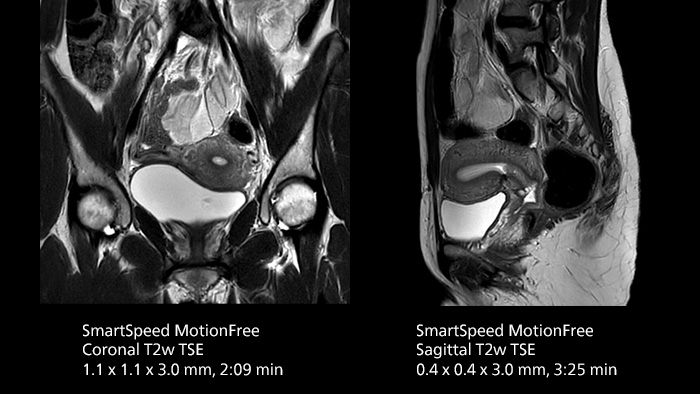

After using Philips SENSE, Mermaid Beach had adopted Compressed SENSE that offers a k-space sampling approach to speed scans while preserving details. “And now SmartSpeed enables denoising the sparse under-sampling in a new way that has allowed us to increase acceleration and bring image quality to a whole new level,” notes Kennedy, “It’s truly revolutionized our MRI work space, especially for difficult patients.”

Philips SmartSpeed has multiple approaches to denoising. Raw k-space data, coil sensitivity and coarse background information are all used and reconstructed with artificial intelligence (AI) to provide true resolution in shorter scan times1 with more sequences. Kennedy states, “I noticed that since the introduction of SmartSpeed, our day is a lot less stressed. When complicated exams need extra time, we just get on with them. And if we need to do something new or extra, we have the time for it and our workflow is still a lot more efficient.”

In addition to workflow benefits, Kennedy highlights the improvement in their diagnostic confidence. “The quality of output is so much higher than what we believed was possible, and it is very consistent across multiple patients. SmartSpeed made it feasible for us to include extra sequences in our exams and still maintain routine scanning times. This allows us to make a surprising number of diagnoses that we couldn’t have appreciated before with our previous protocol. We’ve gotten an extremely positive response from our referrers.”